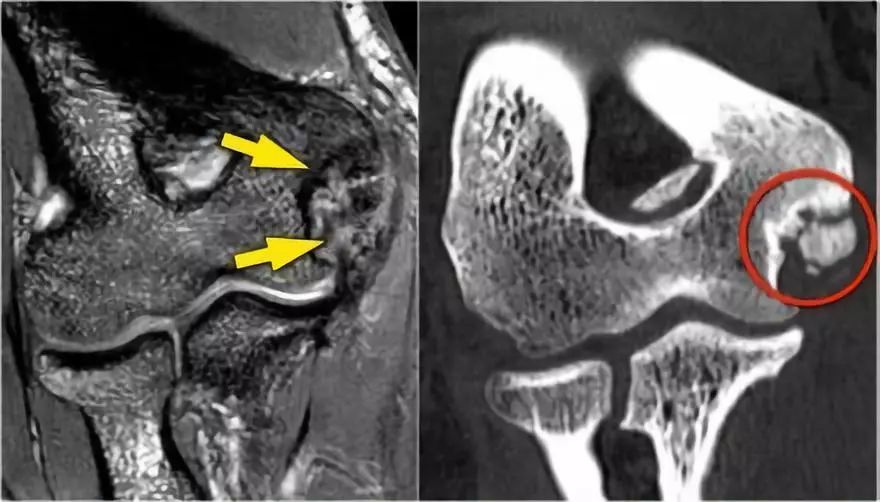

下面的射线照片是一名15岁的棒球运动员,有4年的肘部疼痛史以及最近一次锁定。肱骨小头有一个局部透明度区和一些破碎,这是典型的小头骨软骨病变,

这对于头状骨的是典型的,锁定可能是游离体的结果。

MR-关节造影证实了骨软骨病变。在肱骨和骨软骨病变之间存在钆造影剂,这表明它是不稳定的。注意轴向图像上看到的碎片。

然而他要继续投掷,因为他三年后在17岁时才来就诊。T1W图像显示碎片(黄色箭头),游离体(红色箭头)。T2W图像表明片段不稳定,因为片段和肱骨之间存在高信号。